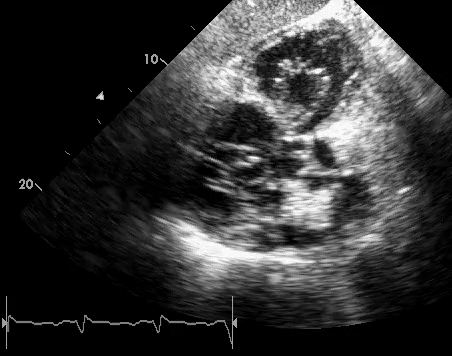

Unlike the aortic and mitral valve it is not possible to visualize all tv leaflets simultaneously in one cross sectional view by standard two dimensional echocardiography 2de either transthoracic or transesophageal due to the position of tv in the far field. An appreciation of the complex and variable anatomy of the tricuspid valve is essential to unraveling the pathophysiology of tricuspid regurgitation. B the relevant anatomy shown from the front view.

Anatomy of the tricuspid valve. The tricuspid valve functions as a one way valve that closes during ventricular systole to prevent regurgitation of blood from the right ventricle back into the right atrium. The valve has anterior posterior and septal leaflets cusps the bases of which attached around the av orifice to the fibrous ring fibrous skeleton of the heart.

The tricuspid valve has an area of 4 to 6 cm square and is located between the right atrium and the right ventricle of the heart. It is the atrioventricular valve that allows blood to flow from the right atrium to the right ventricle. The tricuspid valve lies between the right atrium and the right ventricle and is placed in a more apical position than the mitral valve.